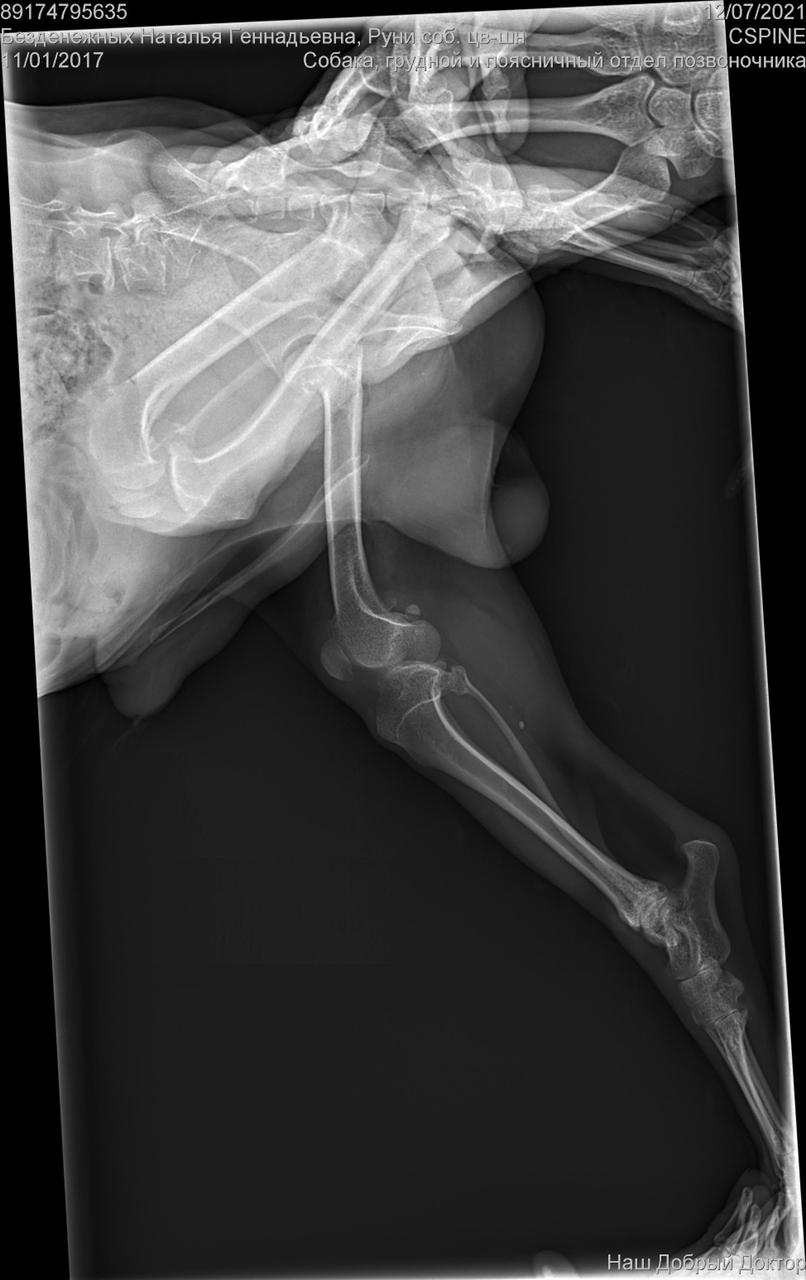

Клиника пообещала отправить рентген на электронку.

Рентген конечно.....

Была травма однозначно. Удалена головка бедра. Мышц нет.

И с позвоночником проблемы. Врачи говорят операции тут не помогут. Если только реабилитация , массаж. Восстановить как то мышцы